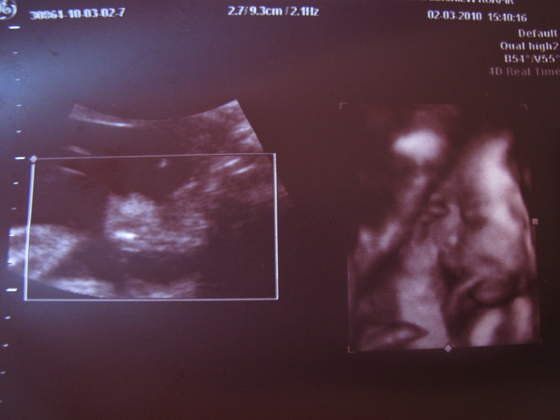

paula-śliczna duża babka i te murzyńskie usta ech!

ale lekarka mnie uspokoiłanadika wstydziosze z Natanka:-)Cudeńko z piękną wagąA co lekarz mówił na tą pępowinę?